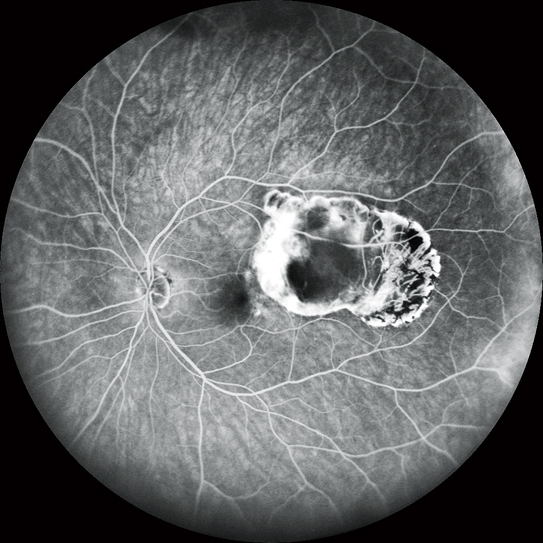

高清動態血管造影

可錄制分辨率高達1,024 x 1,024像素,最長時長為120秒的視頻。在同一次測量中也可分段錄制多個短視頻。

FA和ICG同步血管造影

Mirante操作簡便,可同步拍攝FA和ICG影像。實時IR監測方便操作者在熒光產生前調整拍攝位置,降低錯過血管造影早期階段的風險。

自動增益控制(AGC)可同步調整各個FA和ICG圖像的對比度,使動態血流成像成為一個非常簡便的過程。